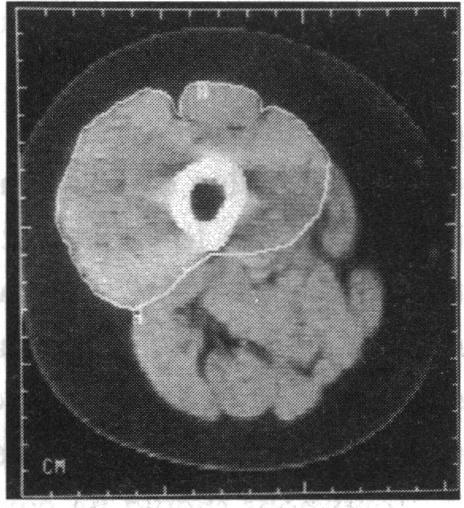

https://cdn.ncbi.nlm.nih.gov/pmc/blobs/7e80/1296173/6afe07a4dd73/jrsocmed00042-0008-b.jpg

https://cdn.ncbi.nlm.nih.gov/pmc/blobs/7e80/1296173/8b6d6dfffa16/jrsocmed00042-0008-a.jpg